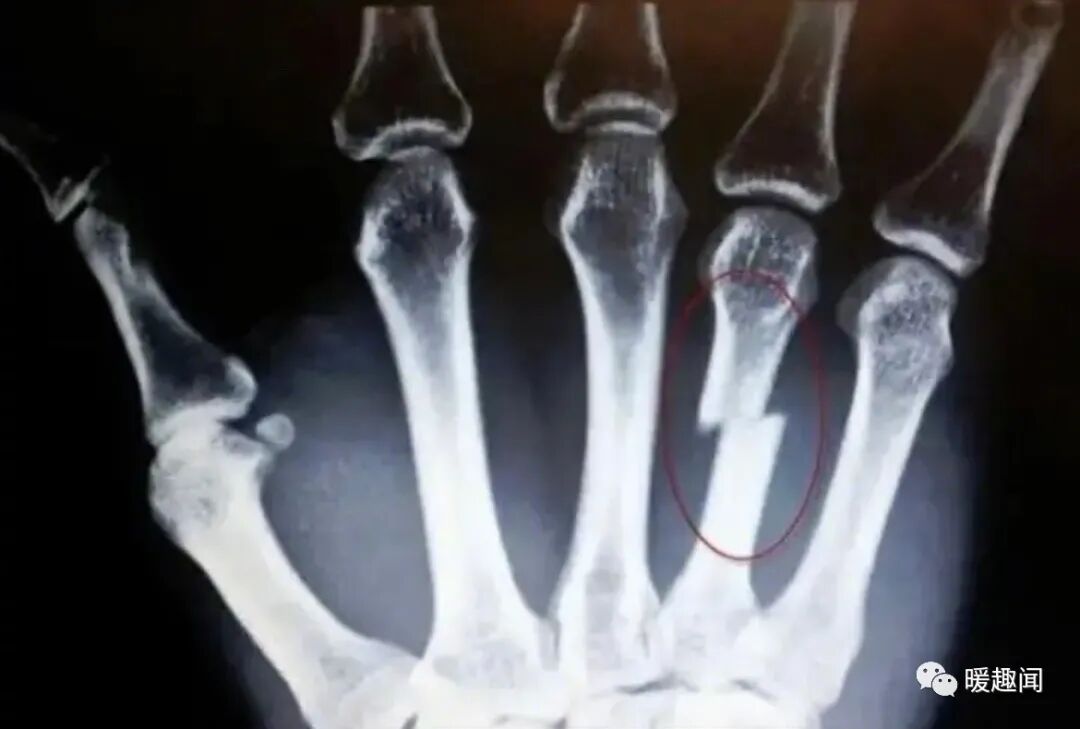

妈妈的防范意识有多强

#你是谁啊 谁是你妈#